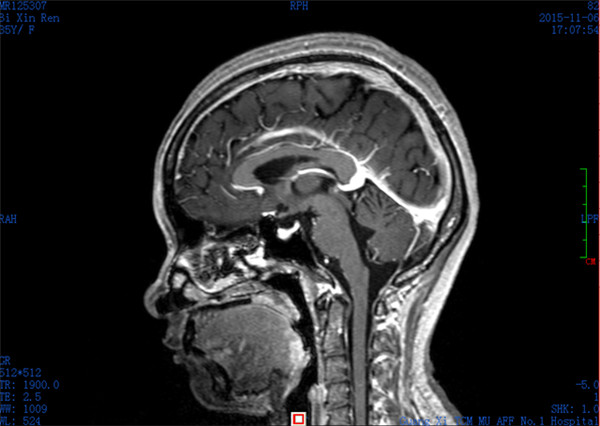

患者闭某,女性,35岁,因产后十余天,进行性头痛就诊收入我科,患者头颅CT证实颅内多发出血灶,静脉窦栓塞可能。患者入院后头痛呈进行性加重,出现反复癫痫,病情危重。我科张高炼主任医师、黄建荣副主任医师查看病人后认为患者属于上矢状窦栓塞,是急性脑卒中的一类,而且已出现梗塞性出血,保守治疗效果极差,既往无血管内治疗的情况下死亡率高达80%以上,即使存活患者也会有严重的神经功能障碍甚至长期昏迷可能,如进病情一步发展,患者势必因颅内高压、梗塞性出血,甚至引起脑疝而导致死亡。

入院CT:脑弥漫点状出血

急诊脑血管造影:上矢状窦闭塞